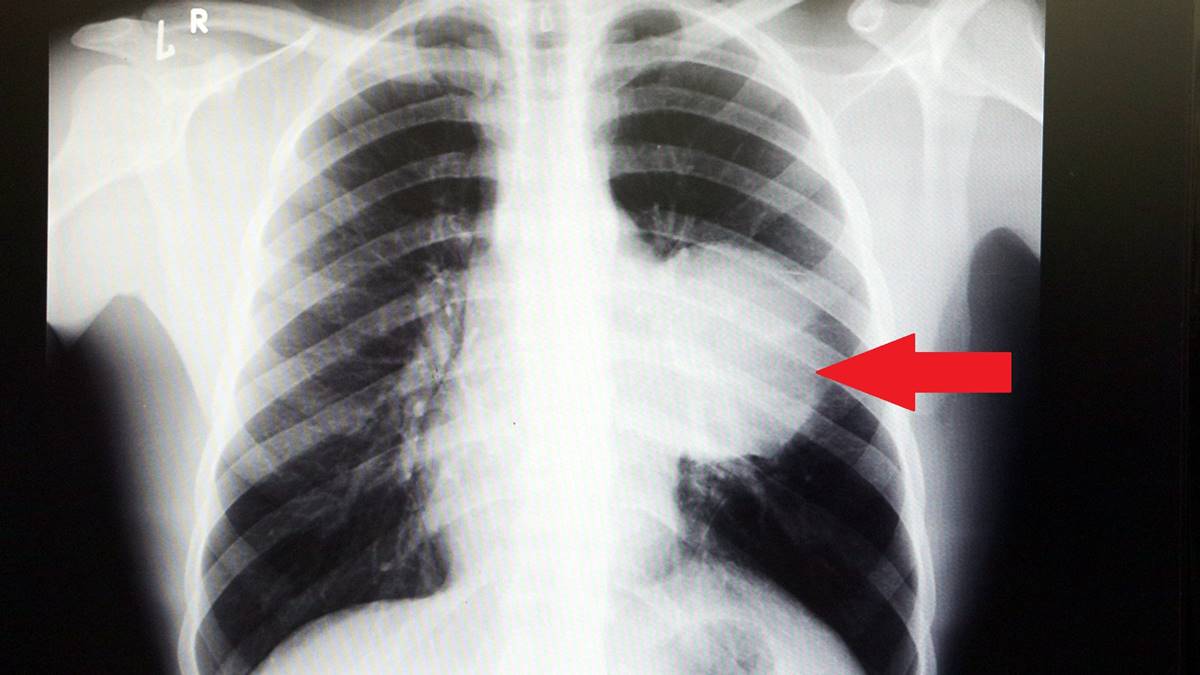

Sol akciğerinin yüzde seksenini kağıt gibi ezen, kalbini göğüs duvarında 12 santim sağa kaydıran ve hem kalbe hem beyne giden ana damarlara baskı yapan 6.5 kilo ağırlığındaki dev tümör, Koşuyolu Yüksek İhtisas Eğitim ve Araştırma Hastanesi Göğüs ve Kalp Damar Cerrahisi ekiplerinin birlikte girdiği operasyonla başarılı şekilde çıkarıldı.

2 ay arayla yapılan tetkiklerinde ve arada cerrahi öncesi küçültme amaçlı kemoterapi almasına rağmen, portakal büyüklüğündeki tümör, irice bir karpuz büyüklüğüne, yaklaşık 6 kilo 300 grama kadar ulaşıyor. Göğüs boşluğunda kemik kafesi içinde olduğu için, itebileceği iki organ var; biri kalp, diğeri de akciğerler.

Soldan sağa doğru büyüdüğü için kalbi tamamen göğüs boşluğunun sağ tarafına itmiş ve kalbe giren ve kalpten çıkan bütün büyük damarları da yer değiştirmenin etkisiyle bükülmüş durumdaydı. Bu nedenle vücuduna yeterince kan gitmiyordu. Ağustos ayının başında portakal büyüklüğündeyken kitle Eylül sonuna irice bir kavun, Ekim ayına geldiğimizde ise bir karpuz büyüklüğüne ulaştığı için, kitlenin büyüme hızı bizi acilen ameliyat yapmaya yöneltti. Yaklaşık 8-10 kat hacimsel olarak artmıştı.

Sol akciğer tamamen ezilmiş ve kağıt haldeydi, alt lobu anestezi ekibimiz yüksek basınç uygulayarak tekrar şişirdi. Çok fazla vaktimiz yoktu, kitle basısından dolayı yaşamla bağdaşmayacağından dolayı hızlı hareket etmek zorundaydık. Bize geldikten üç gün sonra hemen ameliyata aldık çünkü tümörden ziyade onun yaptığı baskıdan kaynaklı hayati riski vardı."

Normalde kalbin özellikle alt ucunun göğüs boşluğunda, iman tahtası orta çizgi kabul edilirse, sola bakar şekilde durduğuna dikkat çeken Prof. Dr. Erdal Taşçı, sözlerini şöyle sürdürdü:

"Ama bu hastada yaklaşık 12-13 s santimlik kalbin alt ucununu yer değiştirmesi ve kalbe giren çıkan bütün damarlar bükülüp kan akımı bozulmuştu. Kalp Damar Cerrahisi ekibi de bizimle beraber ameliyata girdi. Sol akciğerin üst lobu artık geri dönüşümsüz olarak ezildiği için çıkarmak zorunda kaldık.